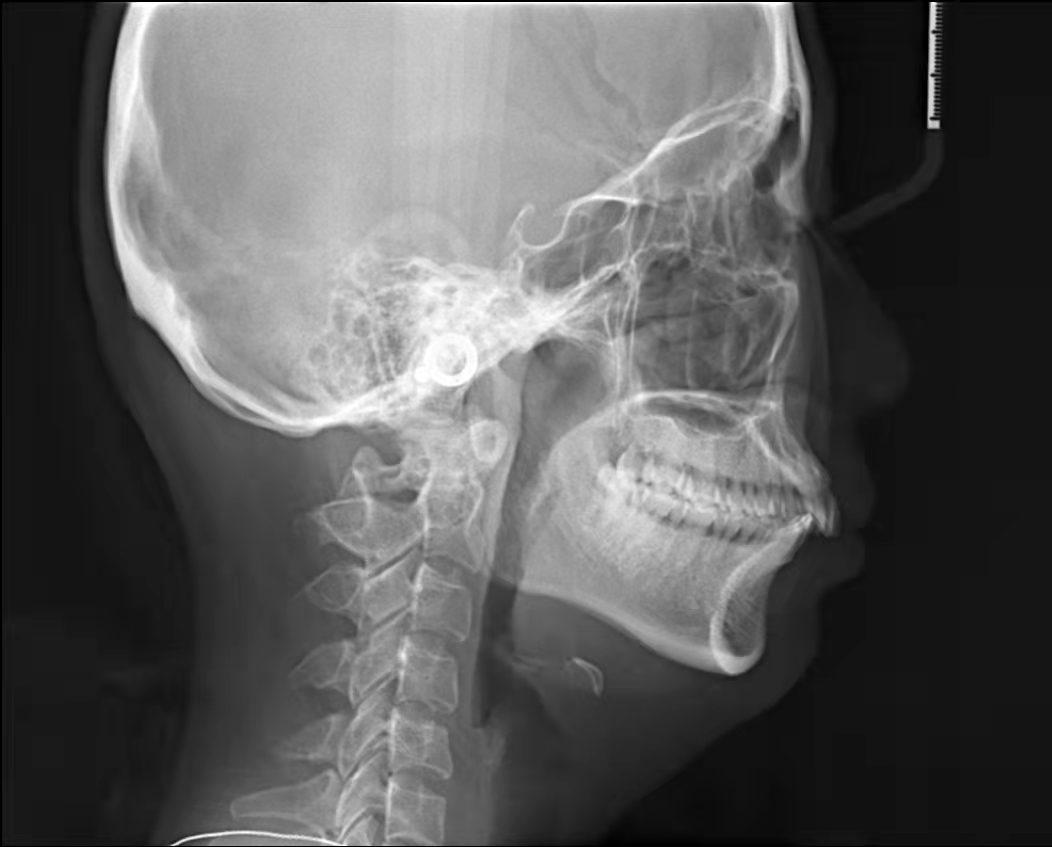

嘴凸不說(shuō)下巴還后縮

4、齙牙造成面部變形。臉型在人體美中占有重要的位置,臉型的美麗與諧調(diào),是由的牙列來(lái)維持的。齙牙咬合受影響,導(dǎo)致面部不協(xié)調(diào),從而加速面部衰竭,由于臉部的骨骼結(jié)構(gòu)也會(huì)影響皺紋形成,齙牙嘴型往前凸,恰好在法令紋位置形成凹陷,法令紋自然會(huì)加深。而且牙槽骨或整個(gè)頜骨因缺乏正常咀嚼氣力的刺激,將會(huì)逐漸蛻變、萎縮,造成下巴的長(zhǎng)度變短,面頰部和四面肌肉松弛,甚至?xí)斐擅娌孔冃巍?/span>